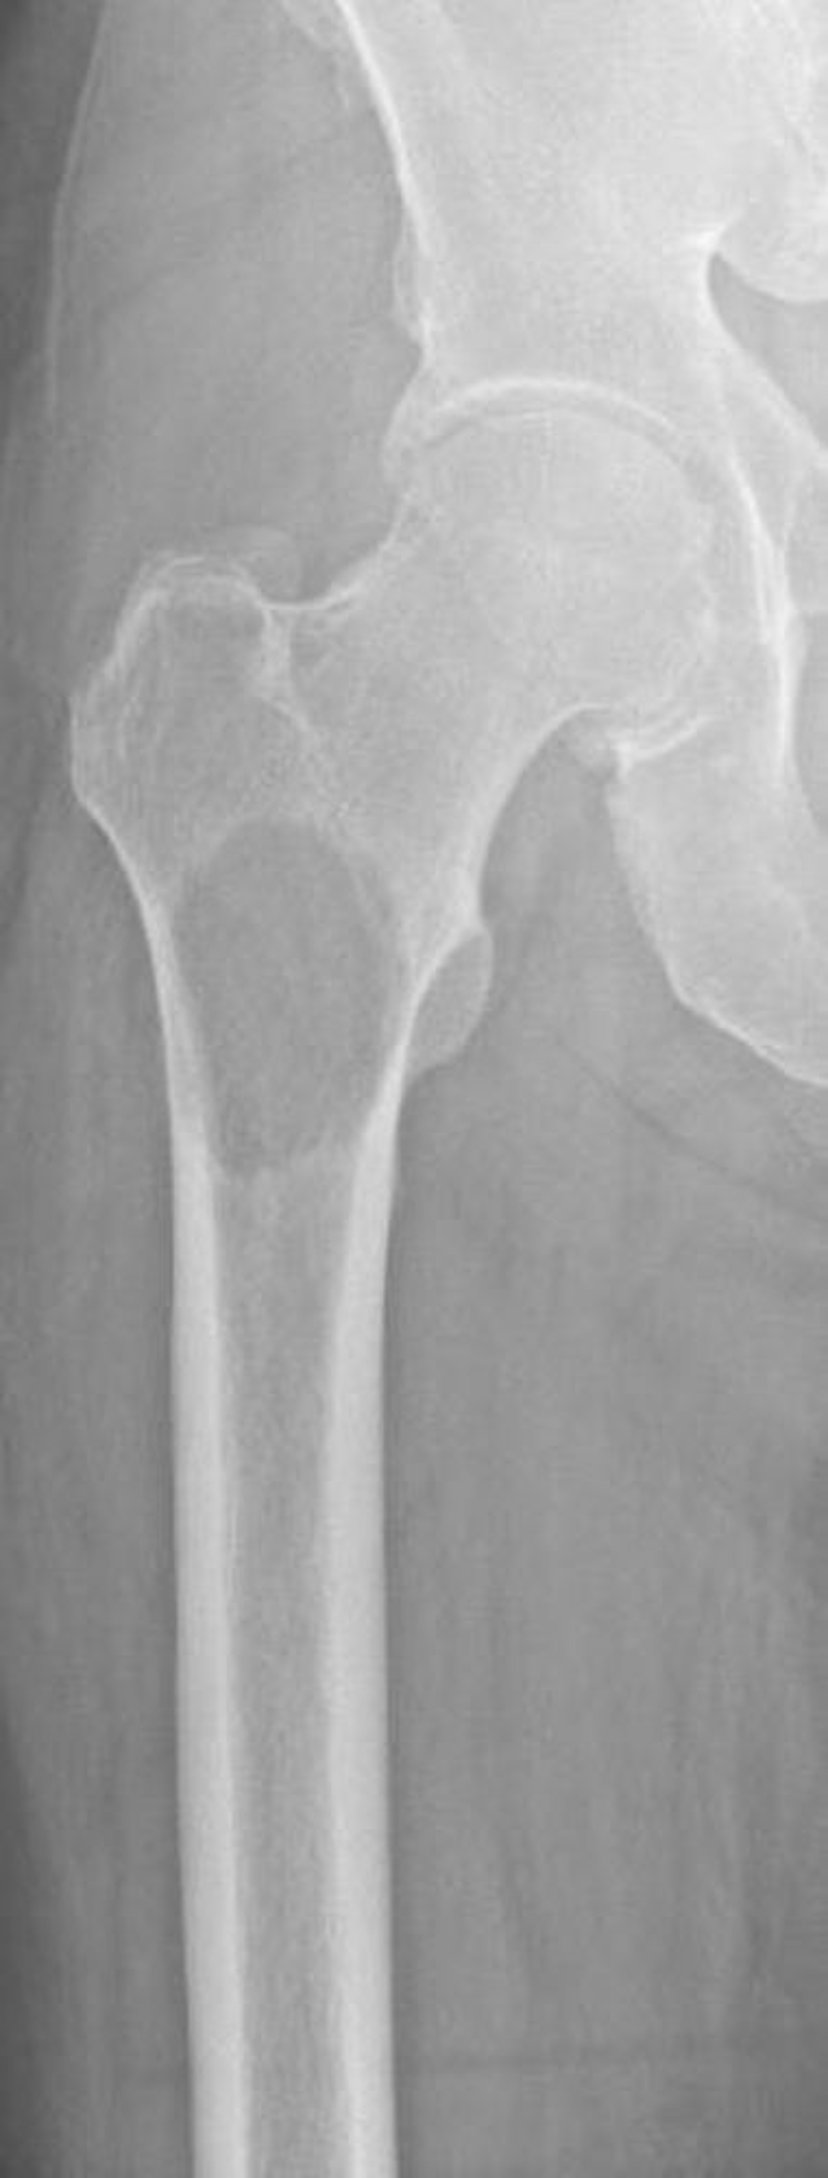

Metastasi litiche nel femore prossimale

Questa immagine mostra la distruzione ossea a causa di una metastasi secondaria al carcinoma a cellule renali nel femore prossimale. La posizione e l'estensione della distruzione ossea rendono il rischio di frattura estremamente elevato (frattura imminente).

Image courtesy of Michael J. Joyce, MD, and David M. Joyce, MD.